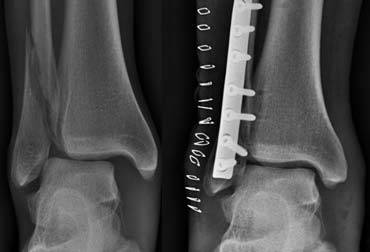

Continue with the images post surgery.

Following osteosynthesis there is obvious widening of the medial and lateral clear spaces (image on the far left).

This indicates that there is a syndesmotic rupture and medial collateral ligament rupture.

The ring is still broken in two places.

The ankle joint is unstable and dislocated.

Resurgery was necessary with placement of a syndesmotic screw to stabilize the ankle joint.